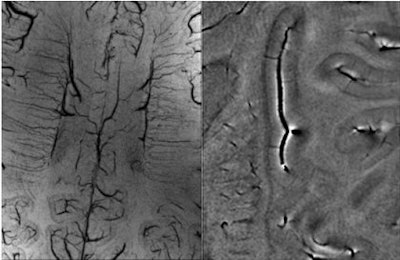

SWI in the brain offers amazing contrast on 1.5-tesla imaging and even better results at higher field strength magnets (3 tesla to 7 tesla). Recent collaborations with Dr. Yulin Ge at New York University in New York City using a 7-tesla system have revealed beautiful differentiation of gray and white matter, as well as the ability to differentiate venules from tissue with SWI.

| With high-field imaging, SWI gets faster because of shorter echo times and better because of increased signal-to-noise ratio. Here are some examples of 7-tesla imaging of the medullary veins, the gray matter and arcuate fibers surrounding the gray matter, pial veins, and venules branching from these veins. The pial veins are on the order of 0.5 to 1 mm, and the venules from 50 to 100 microns. Image courtesy of Dr. Yulin Ge, New York University in New York City, and E. Mark Haacke, Ph.D.; Sam Barnes; and Yingbiao Xu, Wayne State University, Detroit. |